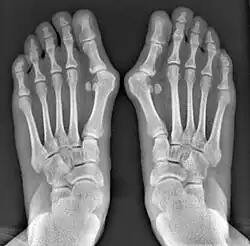

![]() Fig. 8a. Painful hallux valgus and metatarsus primus varus deformity recurrence of left foot after osteotomy surgery | |

- For recurrence correction after osteotomy procedure (Fig. 8)

Late deformity recurrence can happen after osteotomy (bone-breaking) procedures because osteotomy surgeries do not specifically stabilize first metatarsal bone.